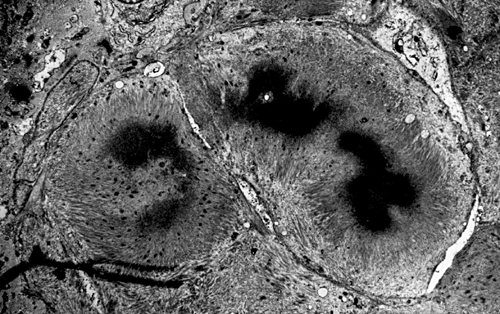

On hematoxylin-eosin stained sections, there is an increased variation of fiber diameter with many atrophic fibers intermingled with fibers of normal caliber. There is no evidence of fiber grouping or perifascicular atrophy. No inflammatory cells are present. There is also mild interstitial fibrosis (Panel A). On higher magnification, many fibers have a round concentric structure (Panel B). Irregular, centrally located depositions are also identified on modified Gomori's trichrome. The concentric nature, however, is not as obvious as in the hematoxin-eosin stained sections (Panel C). Type I and II fibers are not clearly separated in the ATPase preparation at pH 9.4. This is a common situation in chronically ill muscle (Panel D). The type I fibers are unusually dark. There is an increase in the proportion of type I fibers. The atrophic fibers are usually type II fibers. The concentric lesions are found predominantly in type I fibers (Panel E). There is an increase in PAS staining which is consistent with increased glycogen storage (Panel F). No increase in lipid content is demonstrated by oil red O (Panel G). On NADH-TR reaction, the concentric structures appear to have a clear central core that is devoid of enzymatic activity, a rim with intense enzymatic activity and a surround zone with relatively normal reactivity. These features are classic for target fibers (Panel H and I). No deficiency of laminin-2 (merosin) (Panel J) or dystrophin (Panel K) is demonstrated by immunohistochemistry. The central lesions are also immunoreactive for both laminin-2 and dystrophin. Immunohistochemistry for desmin demonstrate a core of strong immunoreactivity and also strong reaction in the sarcoplasmic membrane (Panel L and M). The target structures are also well demonstrated on semithin sections (Panel N). On electron microscopy, z-disc streaming is a common finding and they are often admixed with a substantial amount of dense granular electron dense substance (Panel O and P). There are also numerous cytoplasmic bodies characterized by radiating intermediate filaments (spheroid bodies) (Panel Q and R).